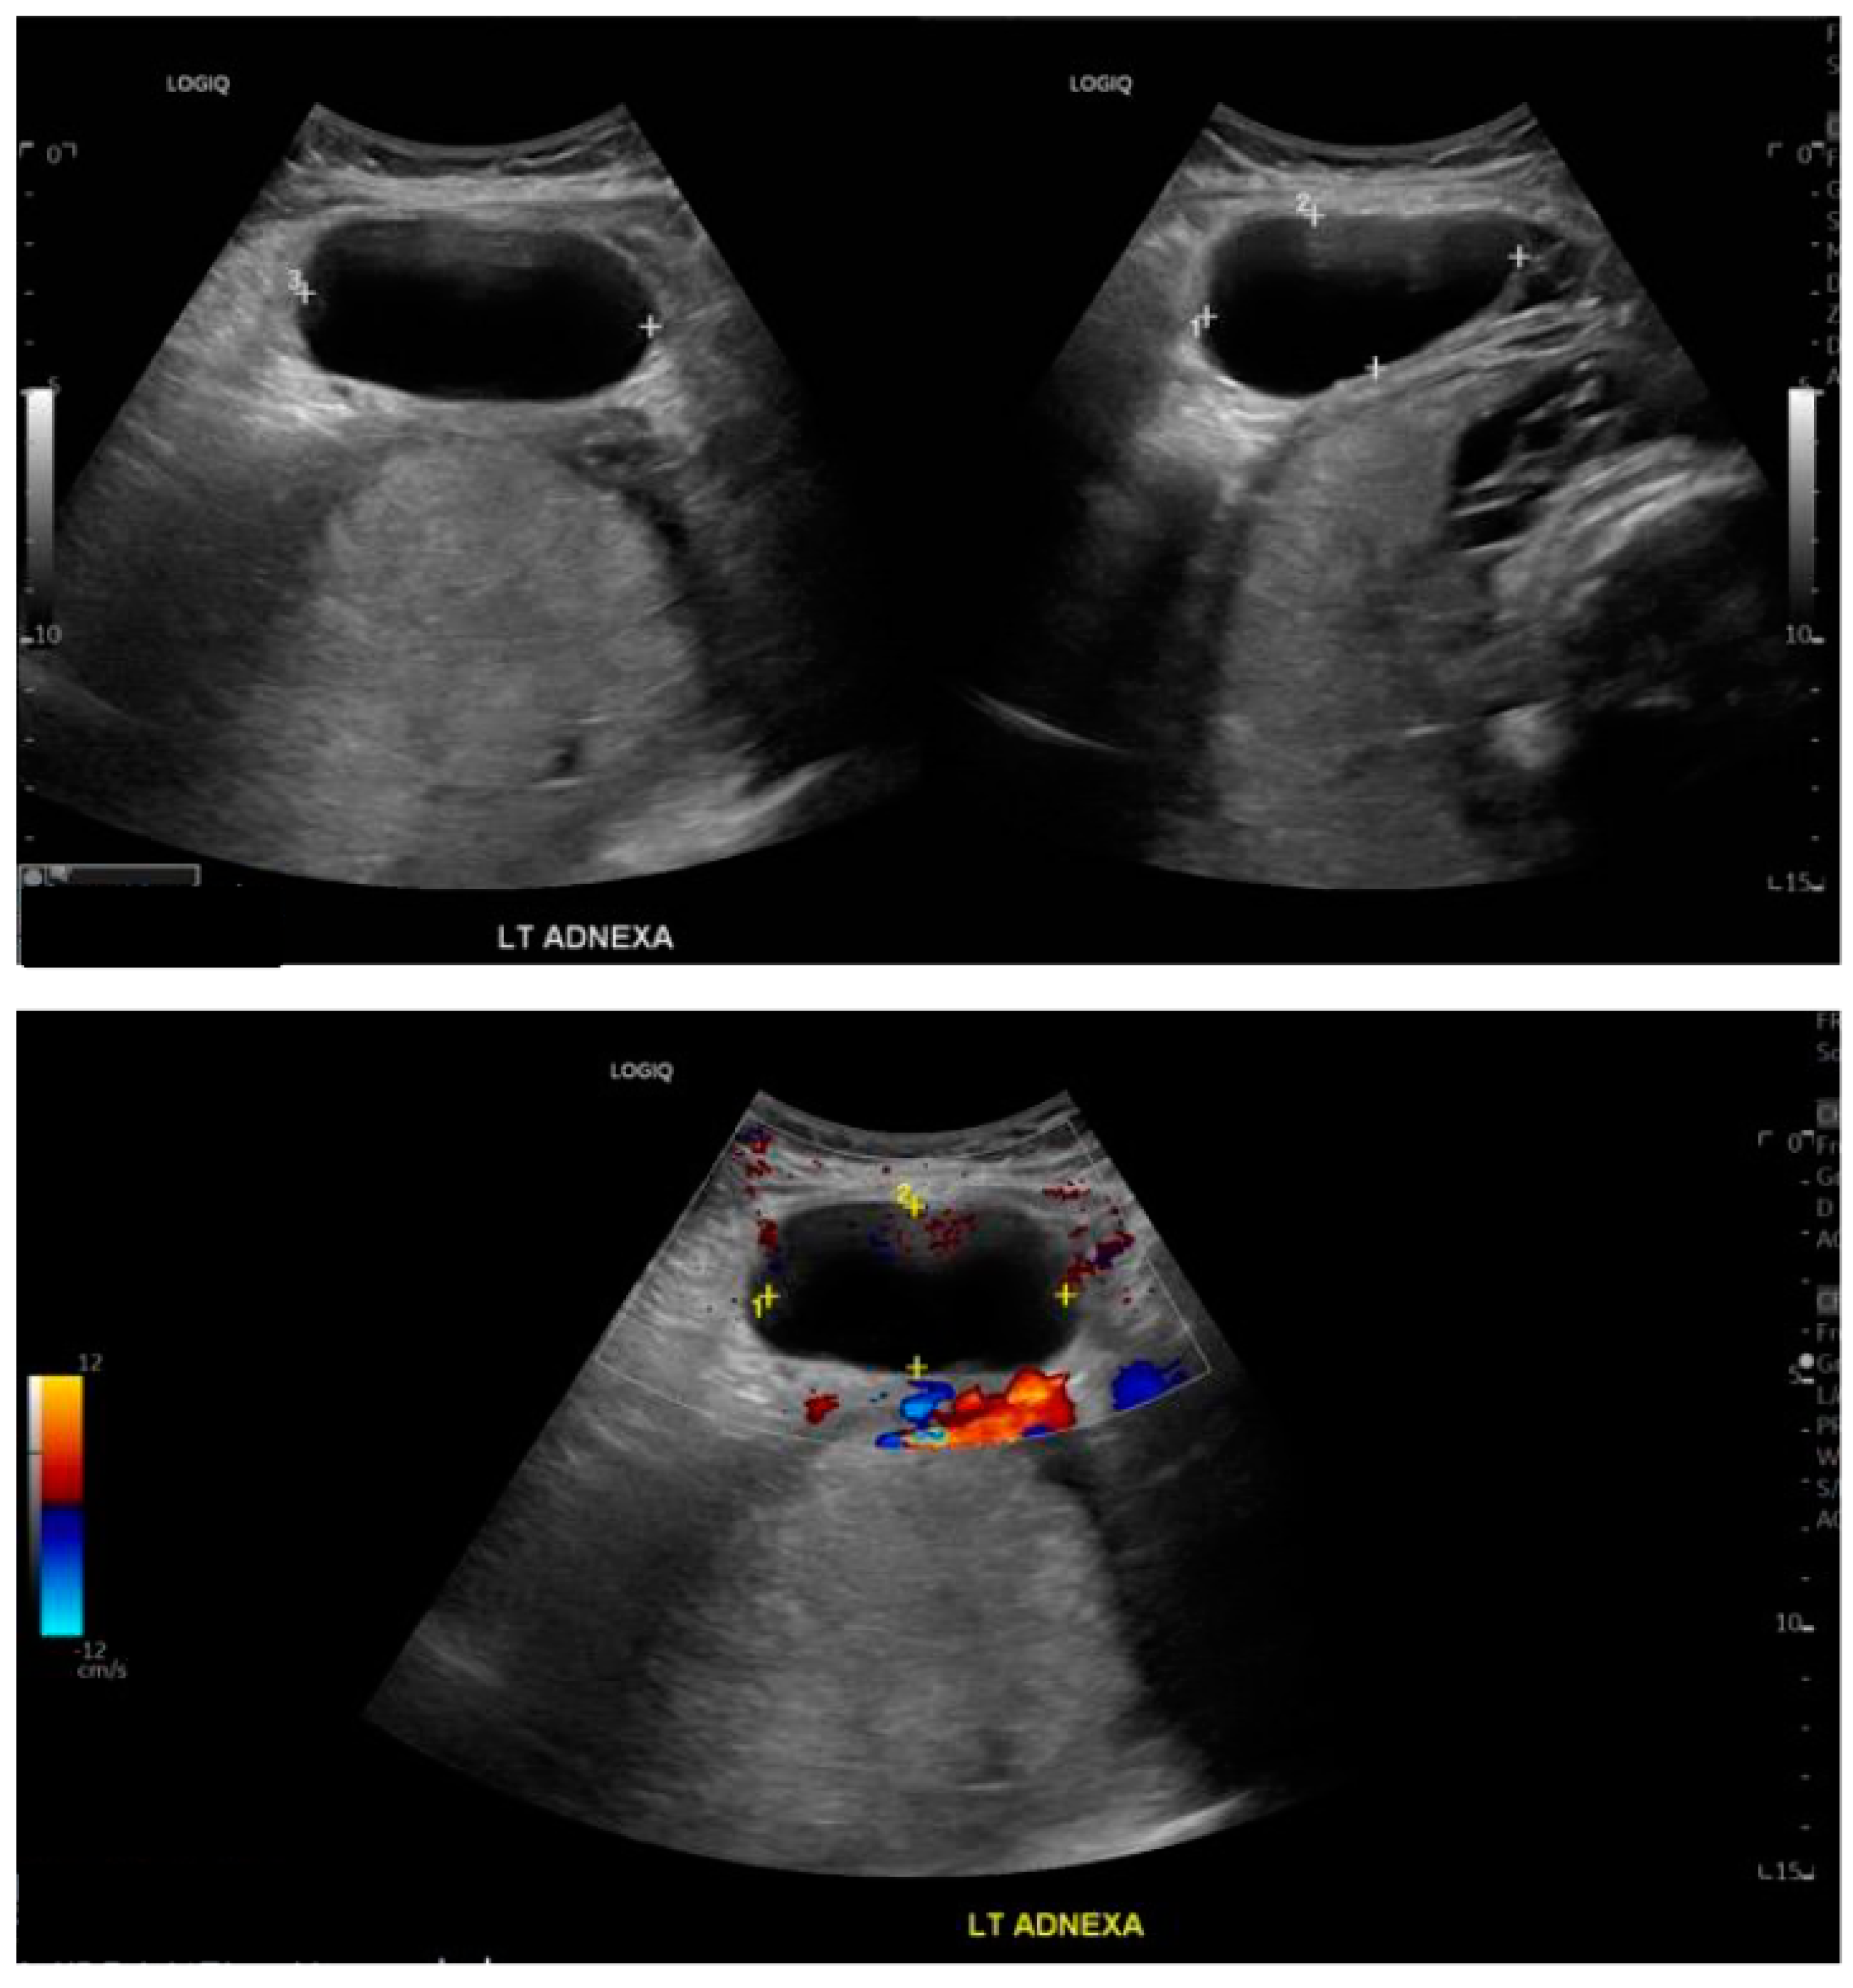

Repeated transabdominal and transvaginal ultrasounds, performed by an experienced sonographer, showed that the known left adnexal cyst remained the same in size and appearance at 63 × 33 × 69 mm, with no features of torsion noted (Figure 3). Specifically, ultrasonographic signs indicative of ovarian torsion, such as the ‘whirlpool sign’, ovarian stromal oedema, absence of detectable Doppler signals in the ovary, and the presence of free fluid in the pelvis, were not observed. There was a discussion about performing an MRI to assess the ovarian cyst, as ultrasound findings were inconclusive. However, due to the rapid change in the clinical picture, an MRI was not performed.

Figure 3. Transabdominal appearance of the left ovarian cyst at 36 + 2 weeks of gestation.